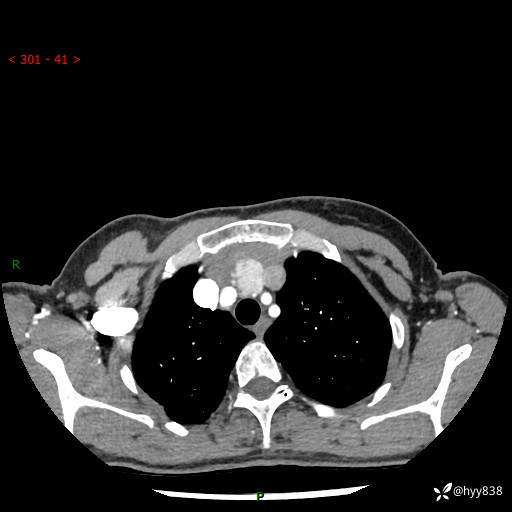

增强动脉期+静脉期